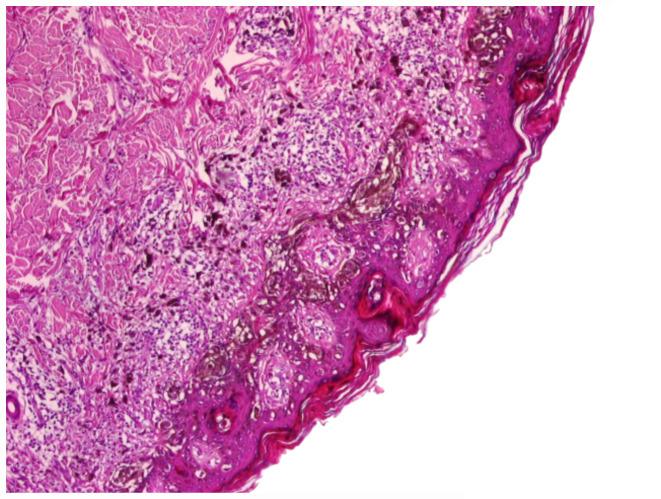

The aim of the present study was to carried out a comparative immunohistochemical evaluation of CD117 (c-Kit), a biomarker that evaluates both tumor progression and prognosis, in different melanocytic lesions, to emphasize the significance of this biomarker in malignant melanoma (MM). The study was performed on 55 cases, represented by a control group, which included 5 cases of simple nevi and 5 cases of dysplastic nevi, as well as a study group consisting of 35 cases of primary MM and 10 metastases (one intestinal, 3 cutaneous - one satellite and two distant as well as 6 in the lymph nodes). The study group included 15 cases of superficial spreading melanoma (SSM), 10 cases of nodular melanoma (NM), 3 lentigo maligna melanoma (LMM), 3 cases of acral lentiginous melanoma (ALM) and 4 cases of amelanotic MM. CD117 was found to be massively involved in the process of tumorigenesis of cutaneous malignancies, being immunohistochemically undetectable in benign neural lesions, but densely expressed in dysplastic lesions and melanoma areas. In invasive cutaneous MMs, CD117 expression tended to decrease with neoplasia progression proceding into the tumorigenic, vertical growth phase, being lower in the profound dermal component of tumors and in nodular MMs. To eliminate the epidermal barriers and gain a proliferative advantage to allow the transition to the vertical growth phase, it seems that MM should lose expression of c-Kit. Cutaneous metastases were found to express CD117 at a level comparable to their primary tumors, suggesting that other mechanisms interfere directly with the metastatic process and not loss of c-Kit expression by itself. CD117 overexpression in cutaneous melanocytic lesions correlates significantly with increased immunostaining intensity, suggesting that the immunohistochemical evaluation of CD117 may be a good method for screening patients, who could benefit from personalized therapy with tyrosine kinase inhibitors.

本研究的目的是对CD117(c-Kit)进行比较性免疫组织化学评估,CD117是一种评估肿瘤进展和预后的生物标志物,在不同的黑素细胞病变中进行评估,以强调该生物标志物在恶性黑色素瘤(MM)中的意义。该研究对55例病例进行,包括一个对照组,其中有5例单纯痣和5例发育异常痣,以及一个研究组,由35例原发性MM和10例转移瘤组成(1例肠道转移、3例皮肤转移——1例卫星灶转移和2例远处转移以及6例淋巴结转移)。研究组包括15例浅表扩散性黑色素瘤(SSM)、10例结节性黑色素瘤(NM)、3例恶性雀斑样痣黑色素瘤(LMM)、3例肢端雀斑样痣黑色素瘤(ALM)和4例无色素性MM。发现CD117大量参与皮肤恶性肿瘤的肿瘤发生过程,在良性神经病变中免疫组织化学检测不到,但在发育异常病变和黑色素瘤区域密集表达。在侵袭性皮肤MM中,随着肿瘤进展进入致瘤性垂直生长期,CD117表达趋于降低,在肿瘤的深层真皮成分和结节性MM中较低。为了消除表皮屏障并获得增殖优势以允许向垂直生长期转变,MM似乎应该失去c-Kit的表达。发现皮肤转移瘤表达CD117的水平与其原发性肿瘤相当,这表明其他机制直接干扰转移过程,而不是c-Kit表达本身的丧失。皮肤黑素细胞病变中CD117的过表达与免疫染色强度增加显著相关,这表明CD117的免疫组织化学评估可能是筛选可能从酪氨酸激酶抑制剂个性化治疗中获益的患者的一种好方法。